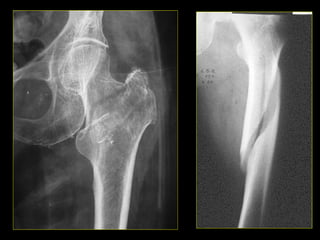

• #11 Fx desplazada 1/3 distal del peroné. Fractura trocánter mayor del fémur.